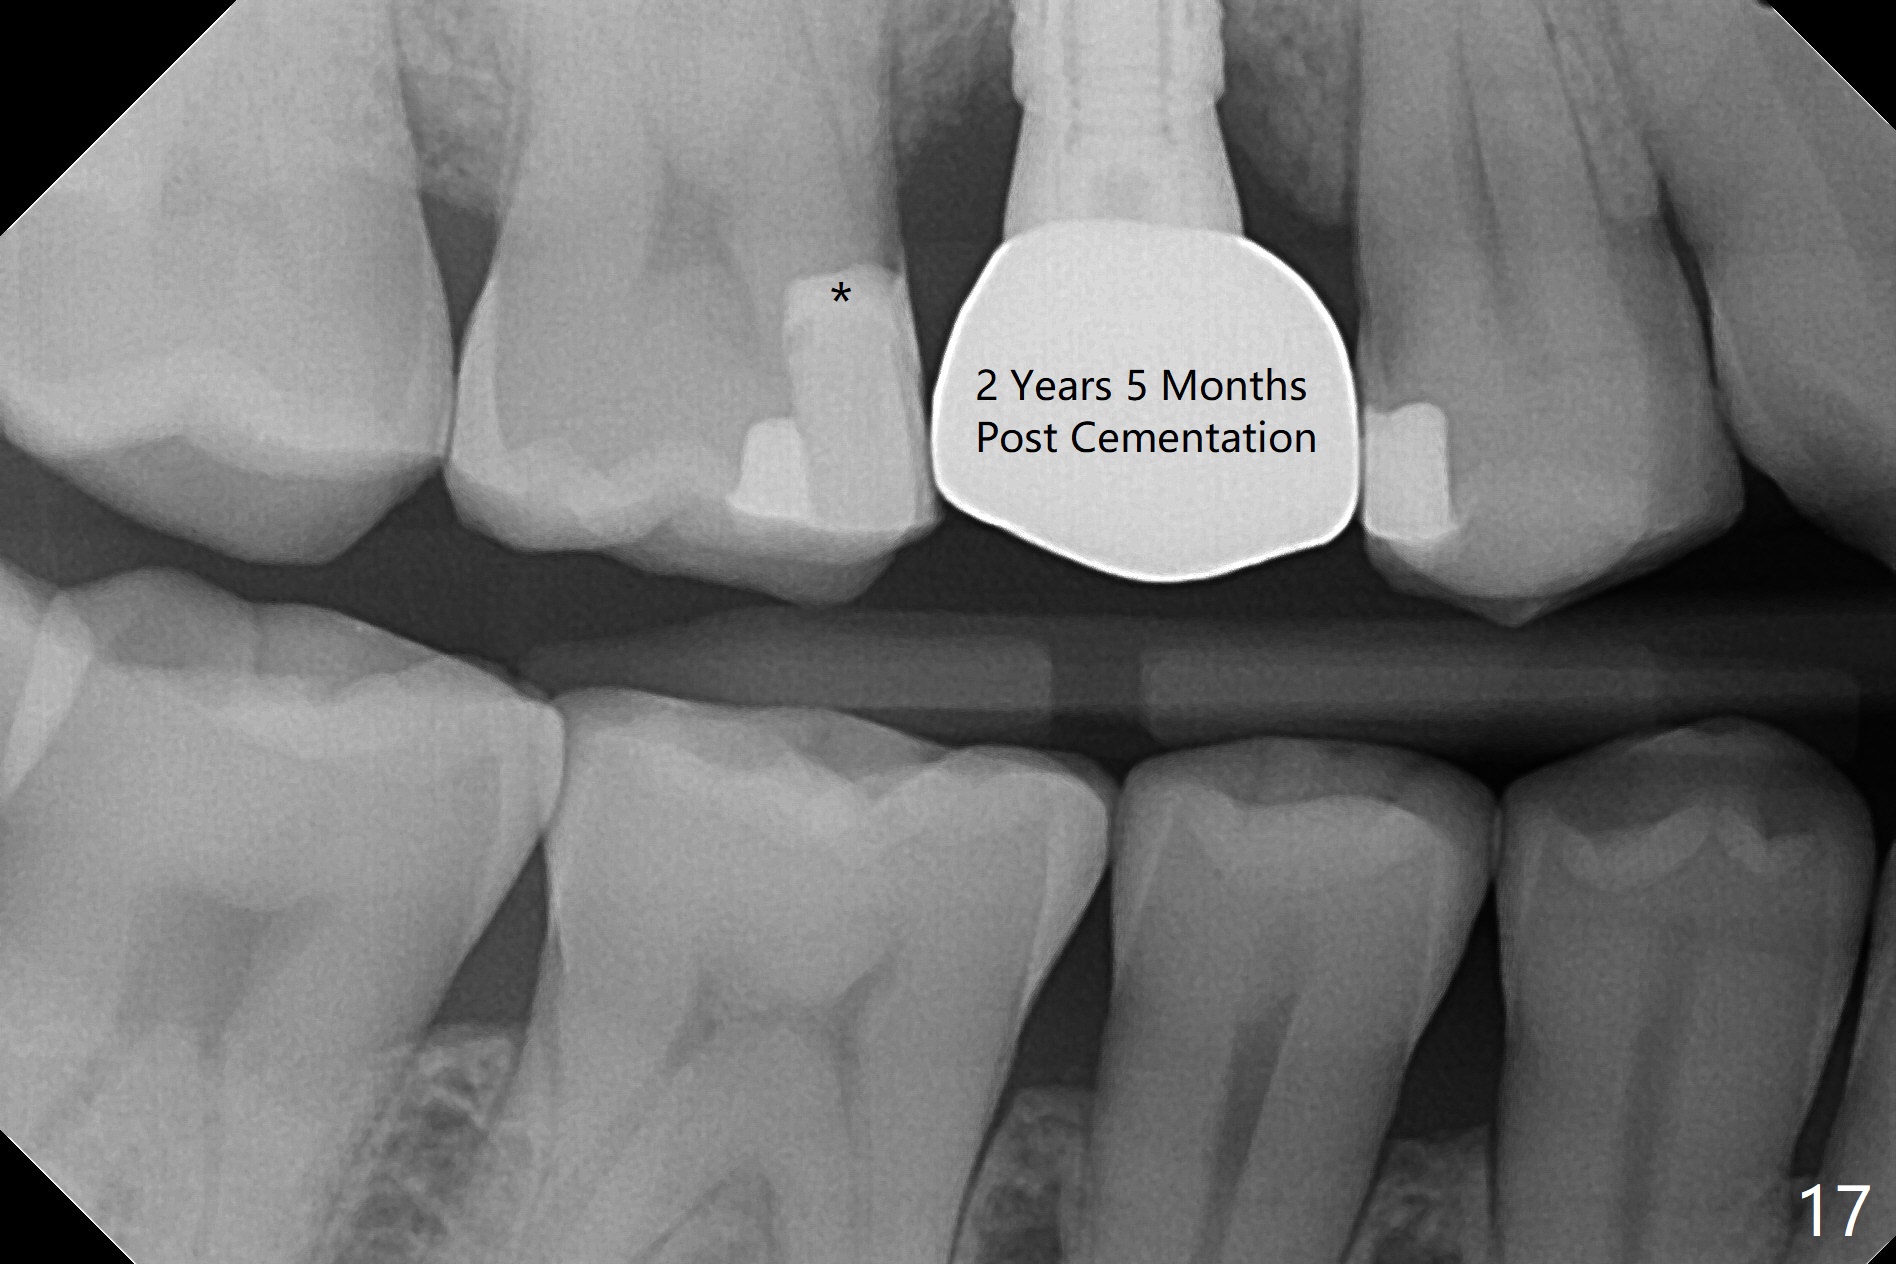

In fact there is a small buccal fistula, which is communicated with the underlying implant threads. Although preop CT shows that the buccal crest is lower than the palatal (3.8x13 mm, Fig.10 P) one, intraop finding of missing buccal plate should dictate a shorter implant (Fig.11) or onlay graft to avoid periimplantitis. Regeneration of the bone plate is limited. Later the fistula disappears with formation of a concavity (Fig.13). There is no symptom. Is bone graft necessary with a remote incision? 3-D images of CT taken 1 year 5 months post cementation show possible mesiobuccal and distopalatal bony defects (Fig.13-16). It is possible that bone graft was placed enough palatal (Fig.16). DO composite at #3 is redo satisfactorily (Fig.17 *).